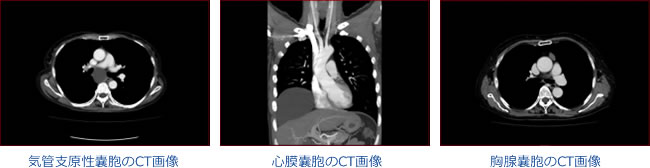

発生部位によって、気管支原性(きかんしげんせい)嚢胞、胸腺嚢胞、食道嚢胞、心膜嚢胞、胸管嚢胞などが報告されています。

先天性嚢胞のCT画像

先天性嚢胞

良性の嚢胞性疾患であっても、非常に大きかったり、炎症を起こしたりしてしまうと、症状を伴うこともあり、注意が必要です。